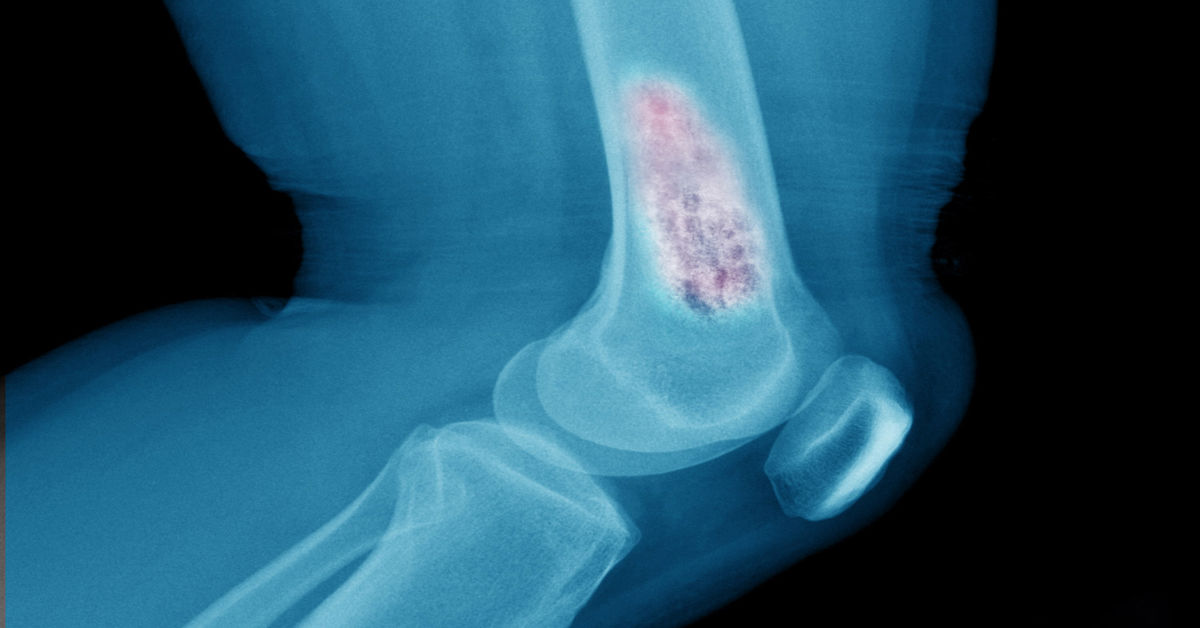

Kemik dokusunda anormal hücre çoğalmasıyla oluşan kitlelerdir. İyi huylu ya da kötü huylu olabilir ve en sık gece artan ağrı ile şişlik görülür. Tanıda röntgen, MR/BT ve gerektiğinde biyopsi kullanılır. Kemik tümörü nedir sorusunun özeti: İyi huylular kürete edilir; kötü huylularda kemoterapi gerekebilir. Uzun süren, istirahatle geçmeyen kemik ağrısında gecikmeden uzman değerlendirmesi önemlidir. Kemik Tümörü […]